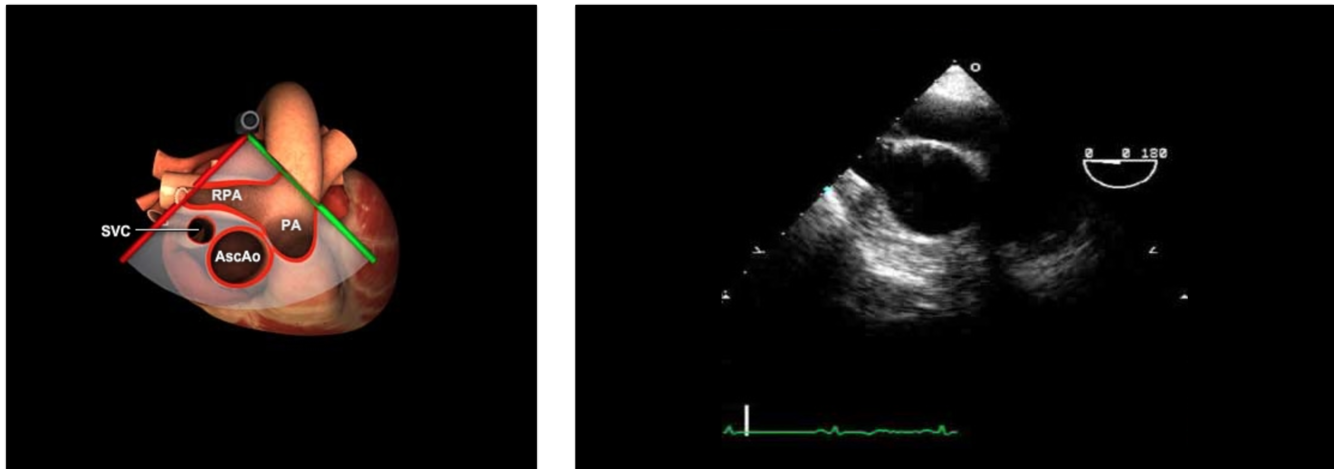

Annulus in red in the photo

Sinus of Valsalva is in Green

Junction in Teal

How do you get to a ME Ascending Aorta Long Axis view?

Insert the probe to the ME, sector depth 8-10cm, angle 0°

Find the ME AV LAX (120°)

Withdraw the probe to bring the right pulmonary artery in view

Decrease omniplane angle slightly by 10-20° to make the aortic wall symmetric